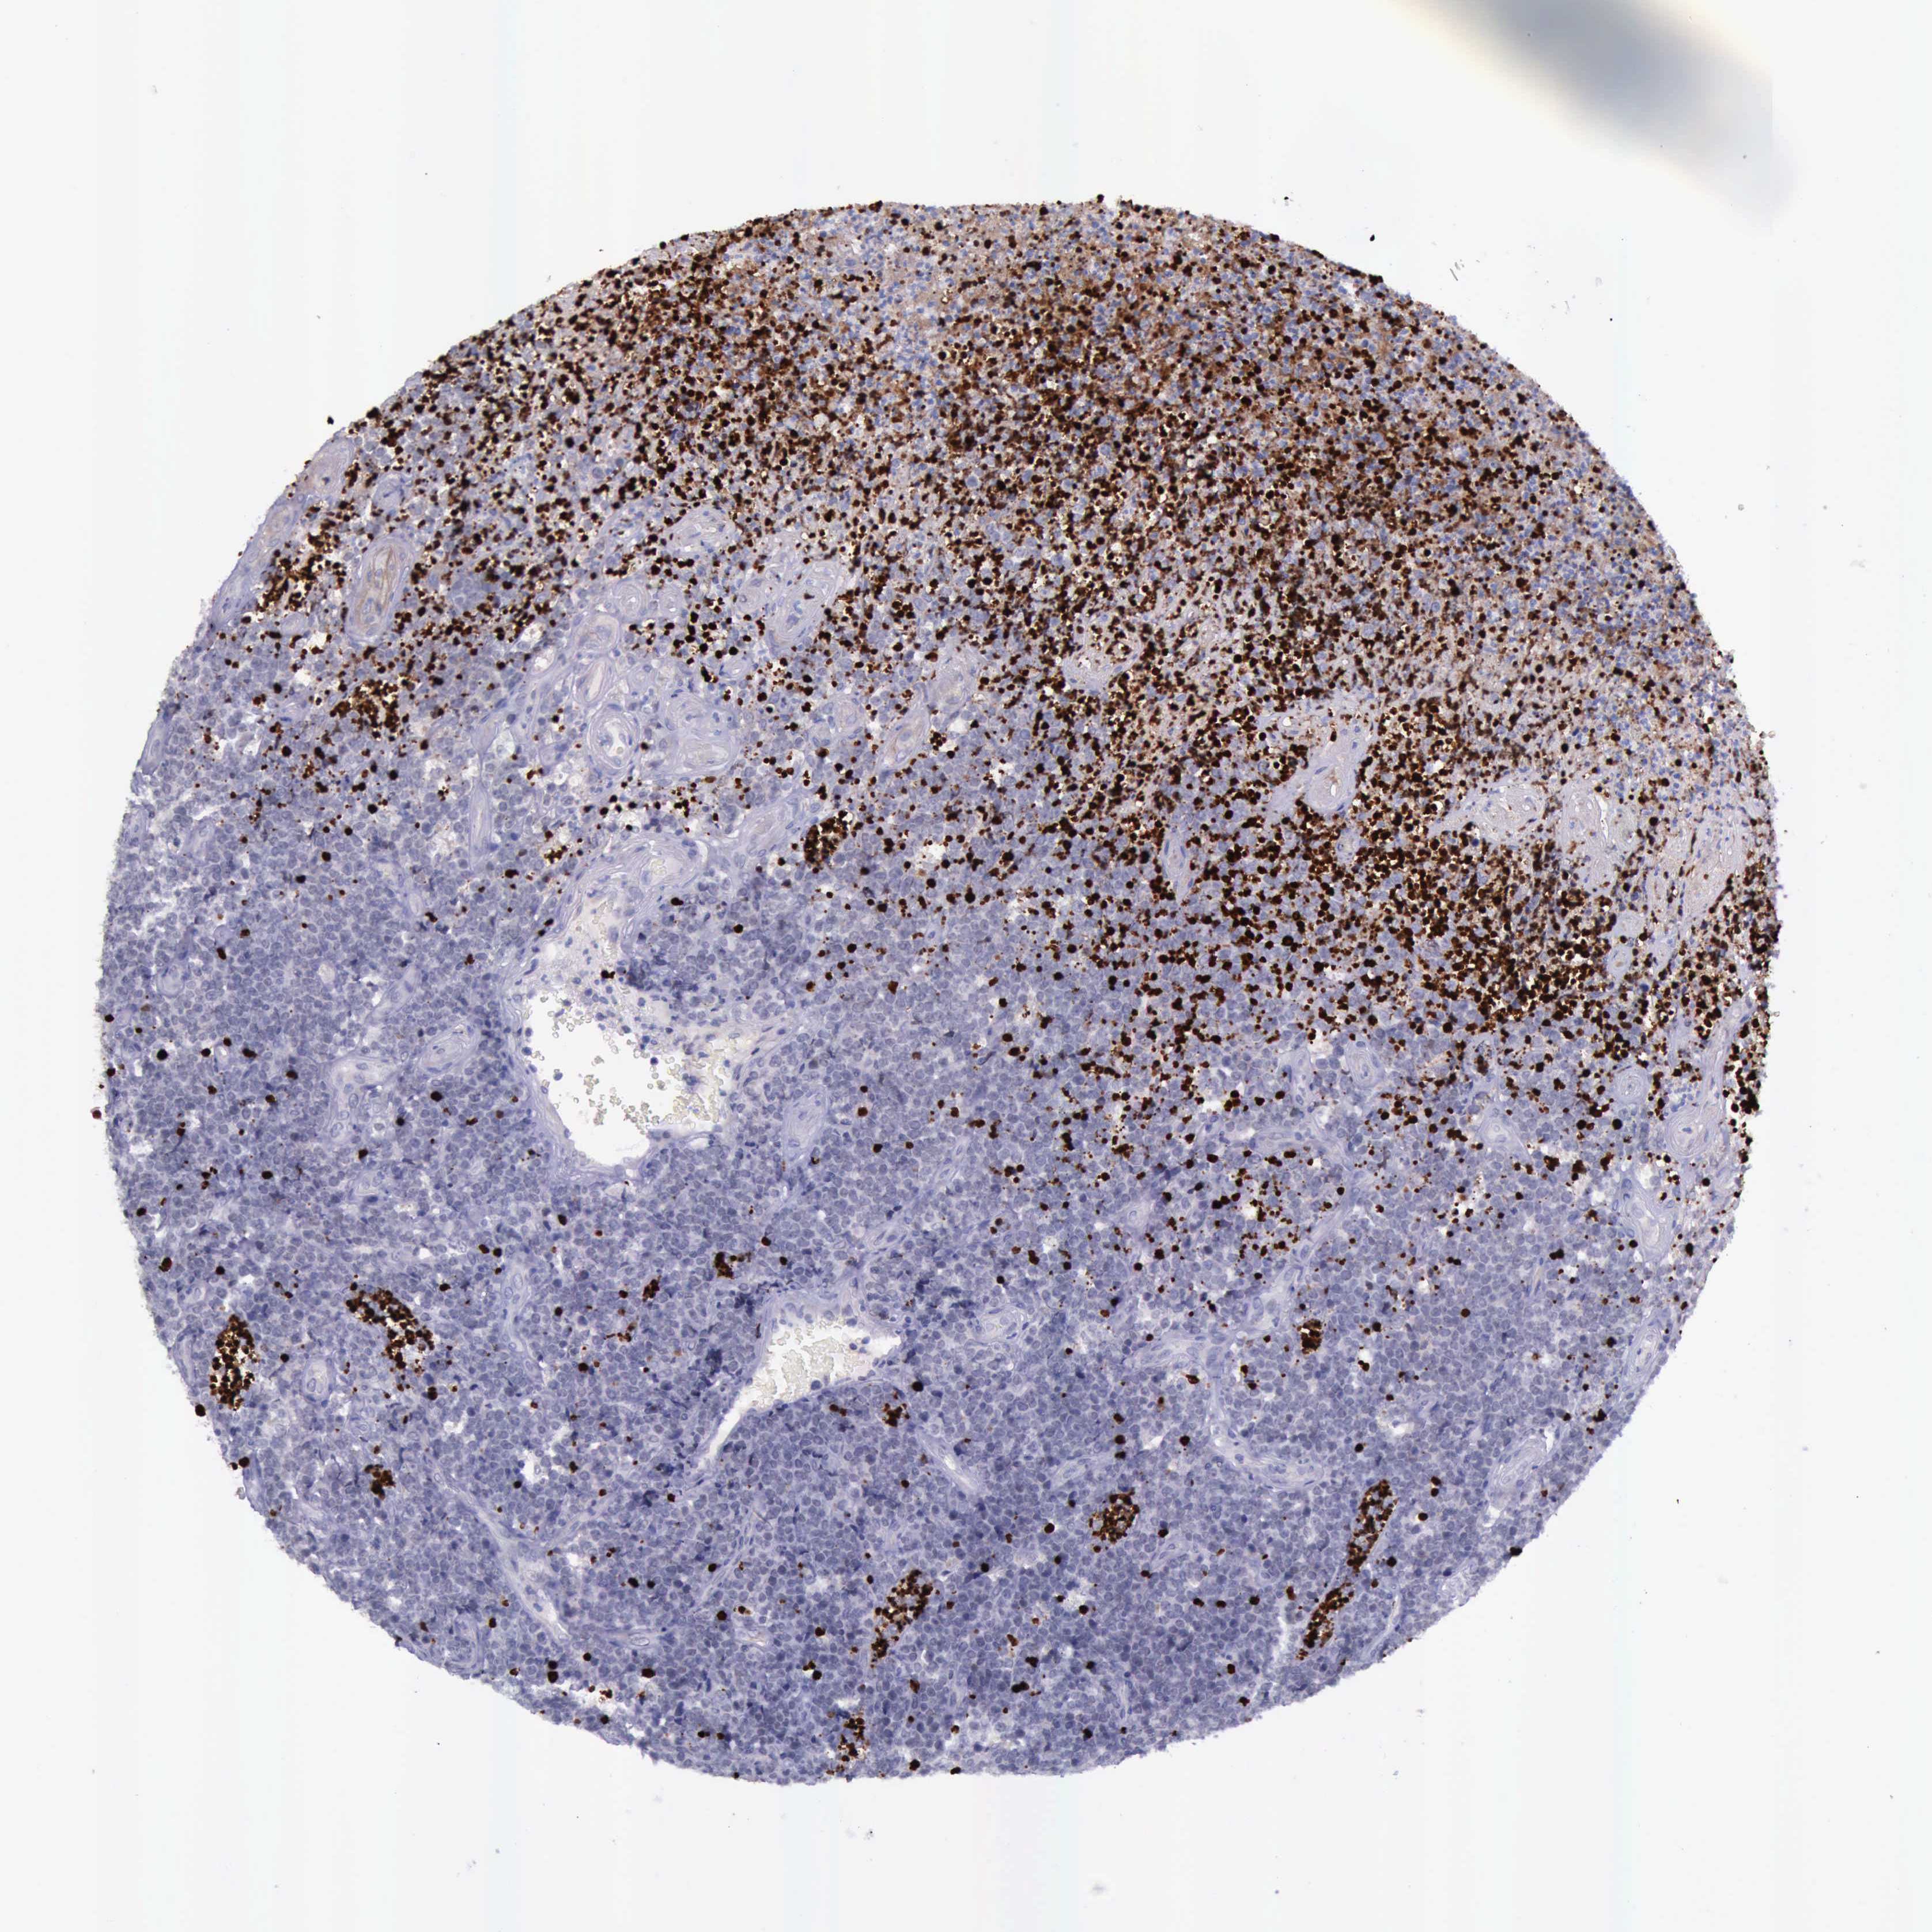

LYMPHOMA